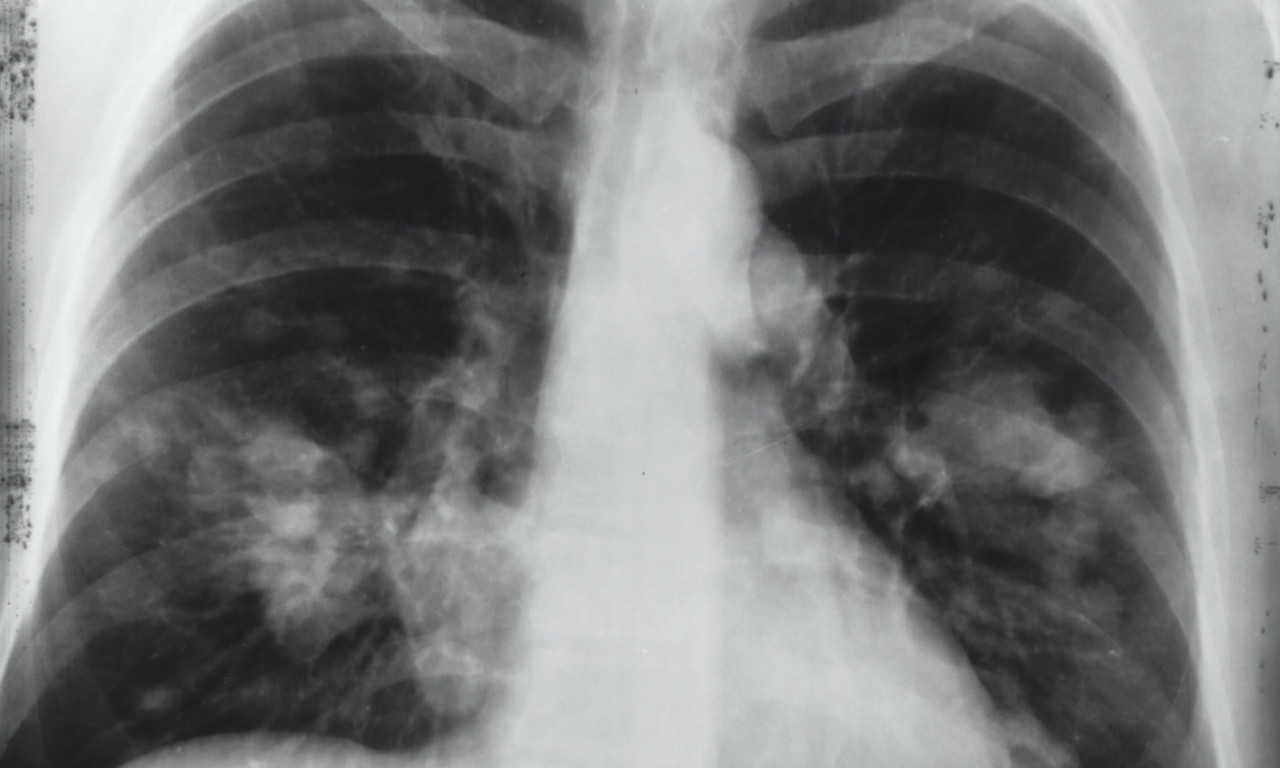

ALARMANTNI PODACI U SRBIJI! Od RAKA PLUĆA oboli 7.000 SRBA godišnje, što nas stavlja na drugo mesto u Evropi

Podatak koji ohrabruje je da se posle pojave prvih simptoma većina pacijenata odmah obrati lekaru